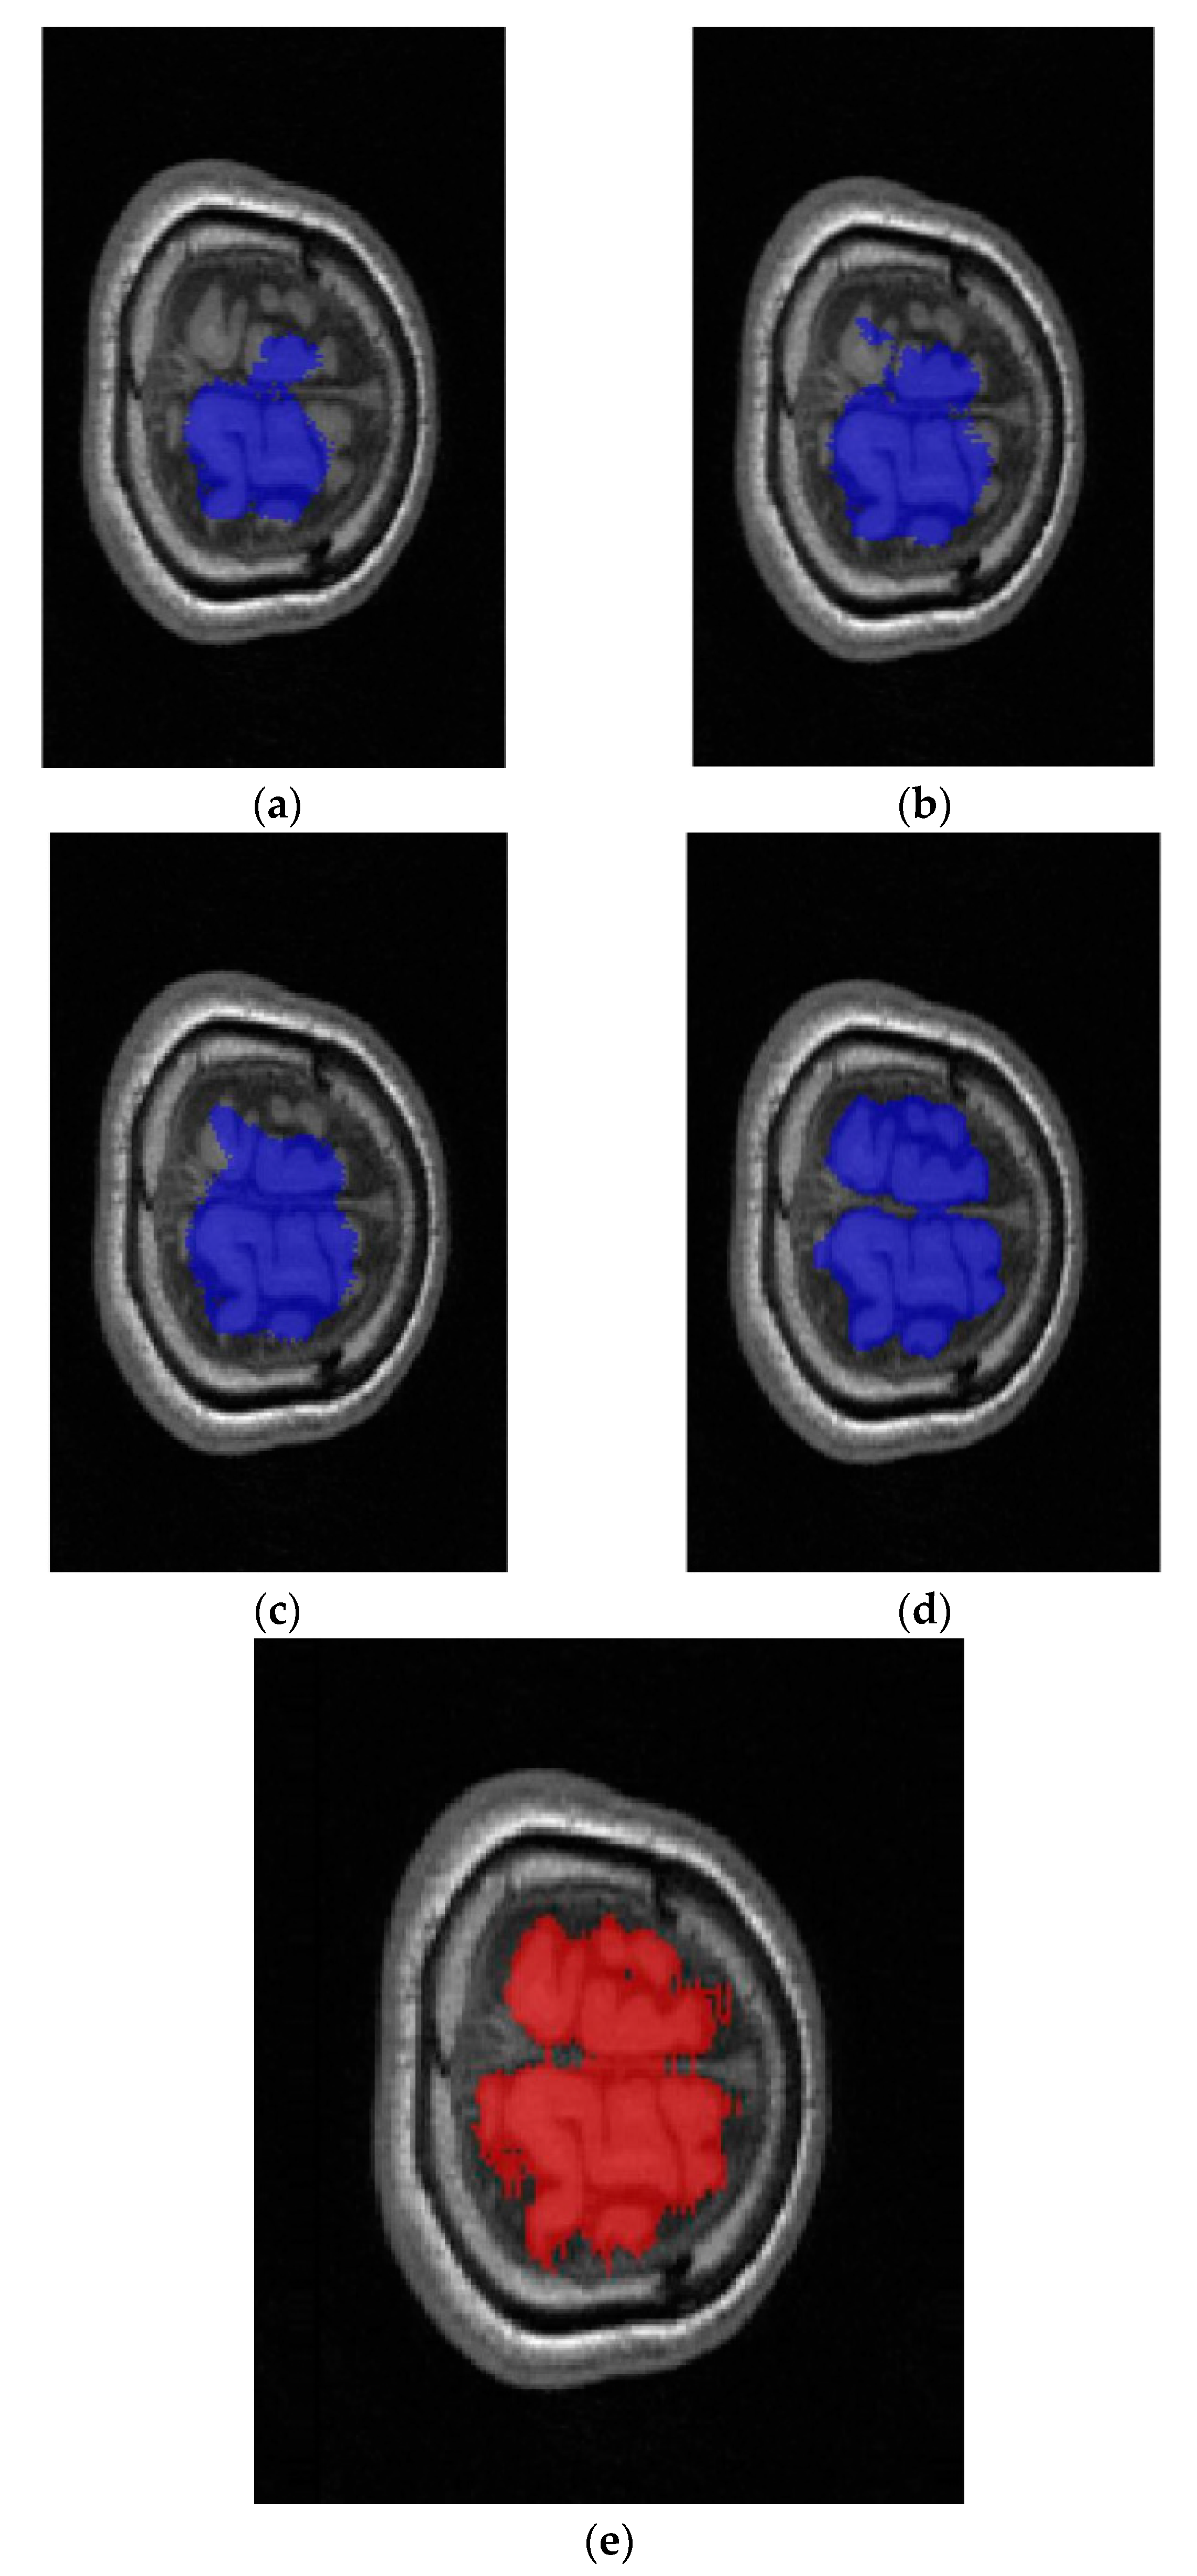

:1. Introduction

2.1. Network Architecture

2.2. Full Image Information Mining with a K-Means Cluster Preprocessing

2.3. Hybrid-U-Net Framework

2.4. Dimensionality Reduction U-Net for 3D MRI Data